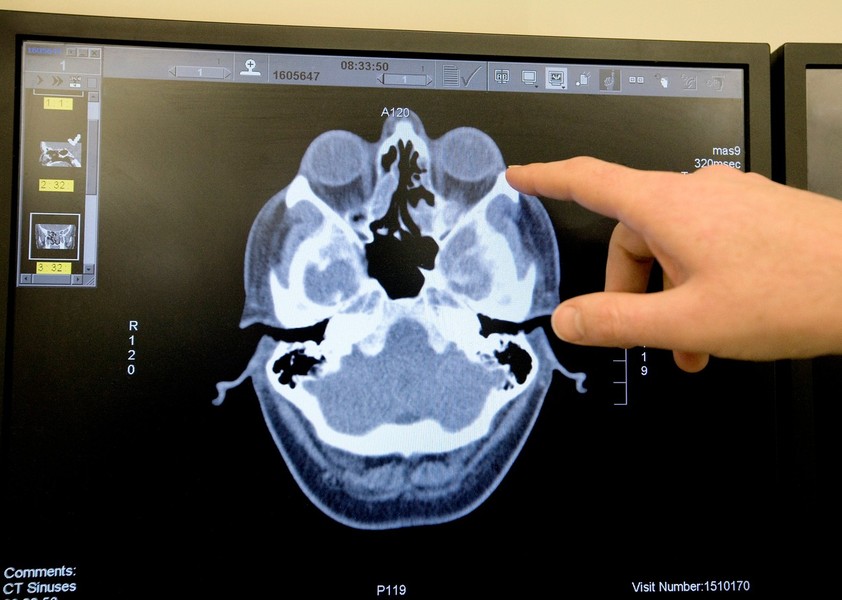

O tomografie computerizată a dezvăluit că bărbatul avea o rană la platoul cribriform, un os care separă cavitatea nazală de creier.

Scurgere de lichid cefalorahidian

Acesta a fost diagnosticat cu o scurgere de lichid cefalorahidian (LCR), o afecțiune rară gravă în care lichidul care protejează creierul și măduva spinării se scurge prin nas.